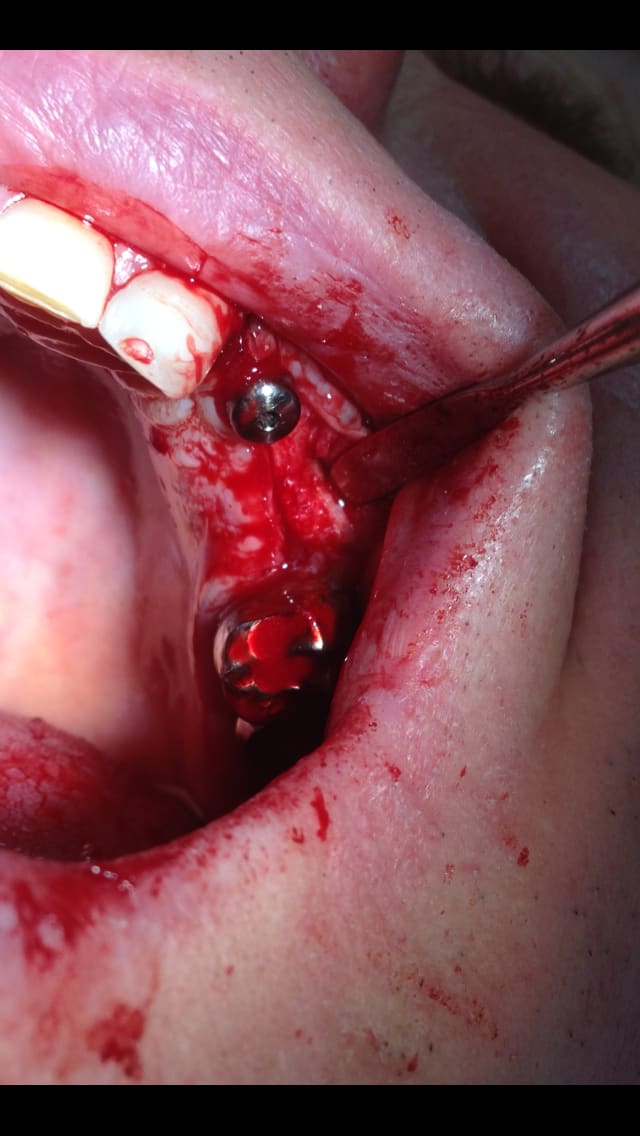

un petit cas pour ressortir ce post...et parce que c'est quand même chaud

incision crestale lame n°15, tatum, spreader Meissinger implants, PX34120 et OP34100 (summer avec eponges)